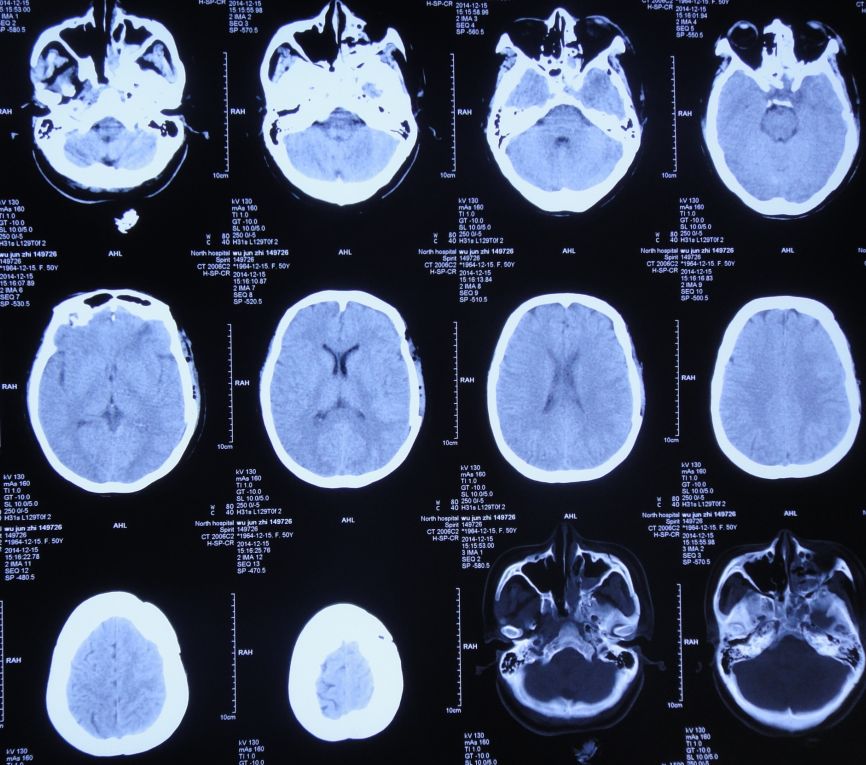

胆囊造瘘术后第56天即2015年12月25日,复查头CT:颅内无异常(图44)。查腹部CT:胆囊造瘘术后,改变(图45)。

图44:2015年12月25日头CT:颅内无异常